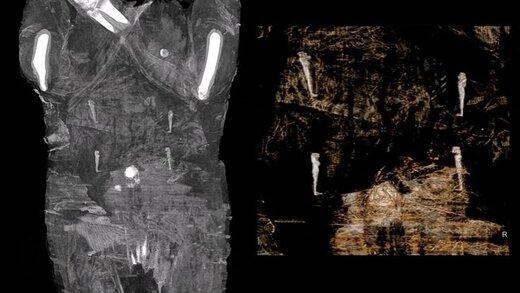

آقای ازموند سپس نتایج بررسیهای تیم تحت رهبری خود را که در ۳۰ دسامبر گذشته در نشریه علوم باستانشناسی منتشر شده را تشریح کرد و گفت: «اسکلت جنین در تصویربرداری رایج که با استفاده از اشعه ایکس انجام میشود، نمودار نمیشوند و به احتمال زیاد به همین دلیل تا کنون تنها یک جسد مومیایی شده باردار کشف شده است.» او افزود: «جسد انسان وقتی که شروع به تجزیه میکند، محیطی اسیدی را ایجاد میکند که موجب میشود، بخشهای استخوانی جنین که هنوز بسیار نرم هستند، نیز شروع کنند به حل شدن در اسید داخل رحم مادر.»

این دانشمند لهستانی توضیح داد که تیم او در نهایت برای دسترسی به روشی برای شناسایی جنین در جسد مومیایی شده، نسبت به بازسازی سه بعدی نتایج به دست آمده از اسکن آن اقدام کردند؛ روشی که در نهایت بافت نرمی را که تصور میشد جنین درون رحم زن مومیایی شده است، نمایان کرد و اجزای بدن او شناسایی شدند.